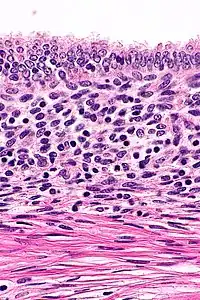

Rokitansky-Aschoff Sinus, Gallbladder Adenomyomatosis

Adenomyomatosis is frequently associated with gallstones and is often diagnosed incidentally, either from a cholecystectomy specimen or autopsy.[4][5][6] No serologic test exists to specify adenomyomatosis and laboratory studies are often normal. Co-existing diseases like cholecystitis may result in abnormal test results, such as elevated levels of white blood cells (leukocytosis), liver enzymes (transaminitis), or bilirubin (hyperbilirubinemia).[5]

Ultrasound is the preferred initial diagnostic choice for suspected gallbladder disease. Several distinct features of adenomyomatosis are discernable using ultrasound, making it a reliable modality for diagnosis.[4][5][6] The most characteristic features seen on ultrasound are the Rokitansky-Aschoff sinuses, which present either as echogenic foci when filled with biliary sludge/gallstones or anechogenic foci when filled with normal bile.[4][5][6] Other key features that may be seen include wall thickening and ring-down artifacts known as "comet tails" (produced by reverberations of sound between the sinuses).[4][5][6] Ultrasound can also distinguish between diffuse, segmental, and localized variants of adenomyomatosis based on morphology.[5][6]

In some cases, gallbladder wall thickening may be seen on ultrasound but is poorly defined and lacking specificity, particularly if the characteristic Rokitansky-Aschoff sinuses are not visualized. This can make it difficult to distinguish adenomyomatosis from other conditions that result in gallbladder wall thickening such as gallbladder cancer.[4][5][6] In these cases, MRI can prove helpful in providing the resolution needed for diagnosis. Especially effective is the T2-weighted MRI at visualizing the pathognomonic Rokitansky-Aschoff sinuses, which appear as round-shaped hyperintense cystic spaces that align in a curvilinear fashion along the gallbladder wall in a pattern described as the ”pearl necklace sign”.[4][5][6]